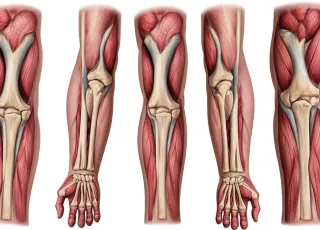

МРТ мягких тканей на Каширском шоссе в Москве применяется при подозрении на наличие каких-либо патологий. Оно используется для установления заболеваний кожи, подкожной клетчатки, сухожилий, суставных капсул, нервных и железистых тканей. Таким образом магнитно-резонансная томография выявляет изменения в мягких тканях человеческого организма, где отсутствует части костного скелета. Это исследование также активно применяется среди спортивных врачей. Они по МРТ отслеживают как протекает процесс восстановления у спортсменов после травм.

МРТ мягких тканей проводится при следующих симптомах и проблемах:

- Боли в мышцах, связках, сухожилиях.

- Подозрение на разрыв или повреждение мягких тканей.

- Диагностика спортивных травм (повреждения плеча, колена, голеностопа).